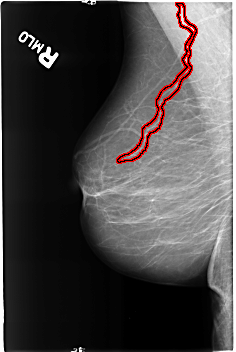

B_3190_1.RIGHT_MLO

FILE: B_3190_1.RIGHT_MLO.OVERLAY

TOTAL_ABNORMALITIES 1

ABNORMALITY 1

LESION_TYPE CALCIFICATION TYPE VASCULAR DISTRIBUTION N/A

ASSESSMENT 2

SUBTLETY 4

PATHOLOGY BENIGN_WITHOUT_CALLBACK

TOTAL_OUTLINES 1

BOUNDARY